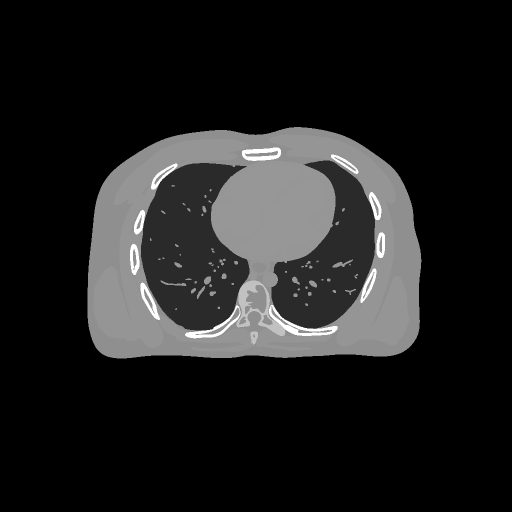

Refer to caption

(a) PSNR = 30

(b) PSNR = 35

(c) PSNR = 37

(d) PSNR = 43

Figure 4: Different method for reconstructing image over 10 repetitions.

FIG 3 give the results of the peak signal-to-noise ratio (PSNR) of the reconstructed images over time on two devices. It can be seen that stochastic algorithms without SVRG can not get high PSNR comapred to that with SVRG and the full batch PDFP. The performance of SVRG-PDFP is as good as PDPF with the device TITAN RTX while SVRG-PDFP behaves the best with the devices with less cores. FIG 4 record the computational time of different algorithms when PSNRs reach 30,35,37,433035374330,35,37,43 on the two different devices. We can see that when the computational resource is powerful (with many parallel cores), the full-batch PDFP can be highly parallized and the stochastic algorithm does not gain in general. However, when the cores number is not very high, stochastic algorithms with SVRG are beneficial compared to deterministic algorithms. FIG 5 gives the reconstructed images with different algorithms and we can see that the one with SVRG-PDFP achieves the highest PSNR as the full batch PDFP.